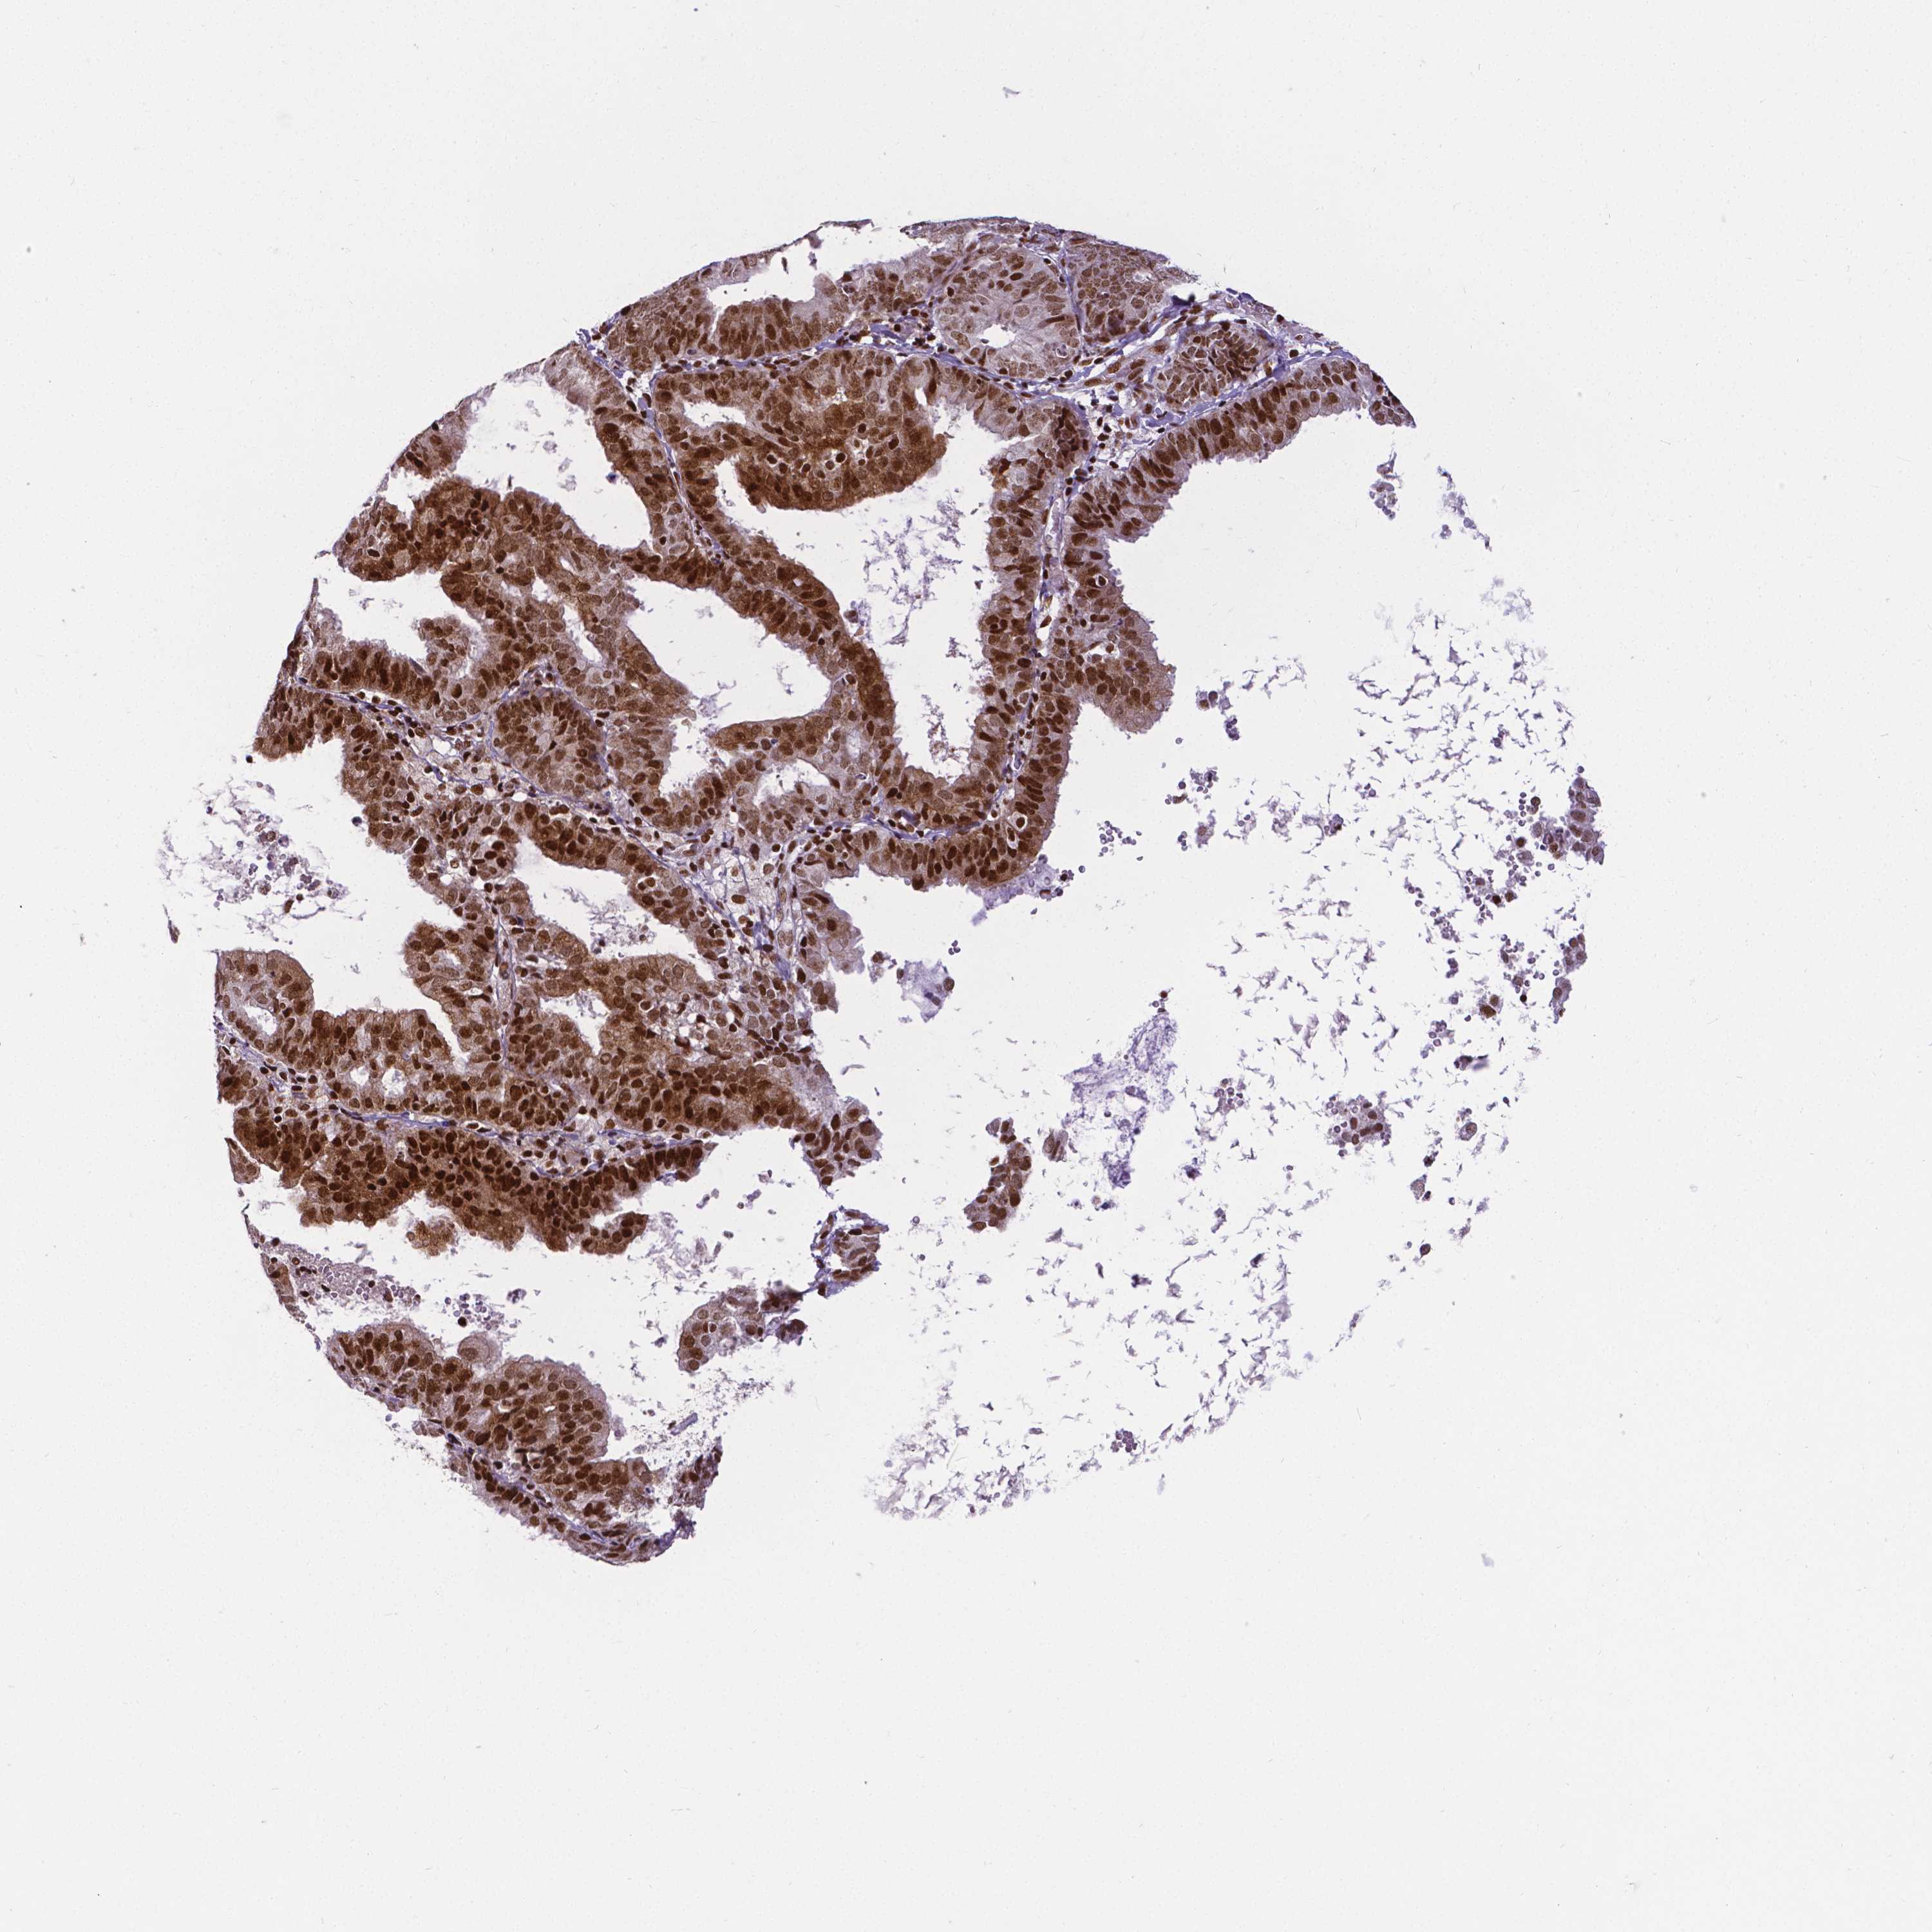

ENDOMETRIAL CANCER - Protein expressioni

A mouse-over function shows sample information and annotation data. Click on an image to view it in a full screen mode. Samples can be filtered based on level of antibody staining by selecting one or several of the following categories: high, medium, low and not detected. The assay and annotation is described here.

Note that samples used for immunohistochemistry by the Human Protein Atlas do not correspond to samples in the TCGA dataset.

Antibody stainingi

Antibody staining in the annotated cell types in the current human tissue is reported as not detected, low, medium, or high, based on conventional immunohistochemistry profiling in selected tissues. This score is based on the combination of the staining intensity and fraction of stained cells.

Each image is clickable and will lead to virtual microscopy that enables deeper exploration of all samples and also displays staining intensity scores, fraction scores and subcellular localization as well as patient and tissue information for each sample.

Antibody HPA004122

Antibody CAB062550

Antibody CAB068181

Antibody CAB068182